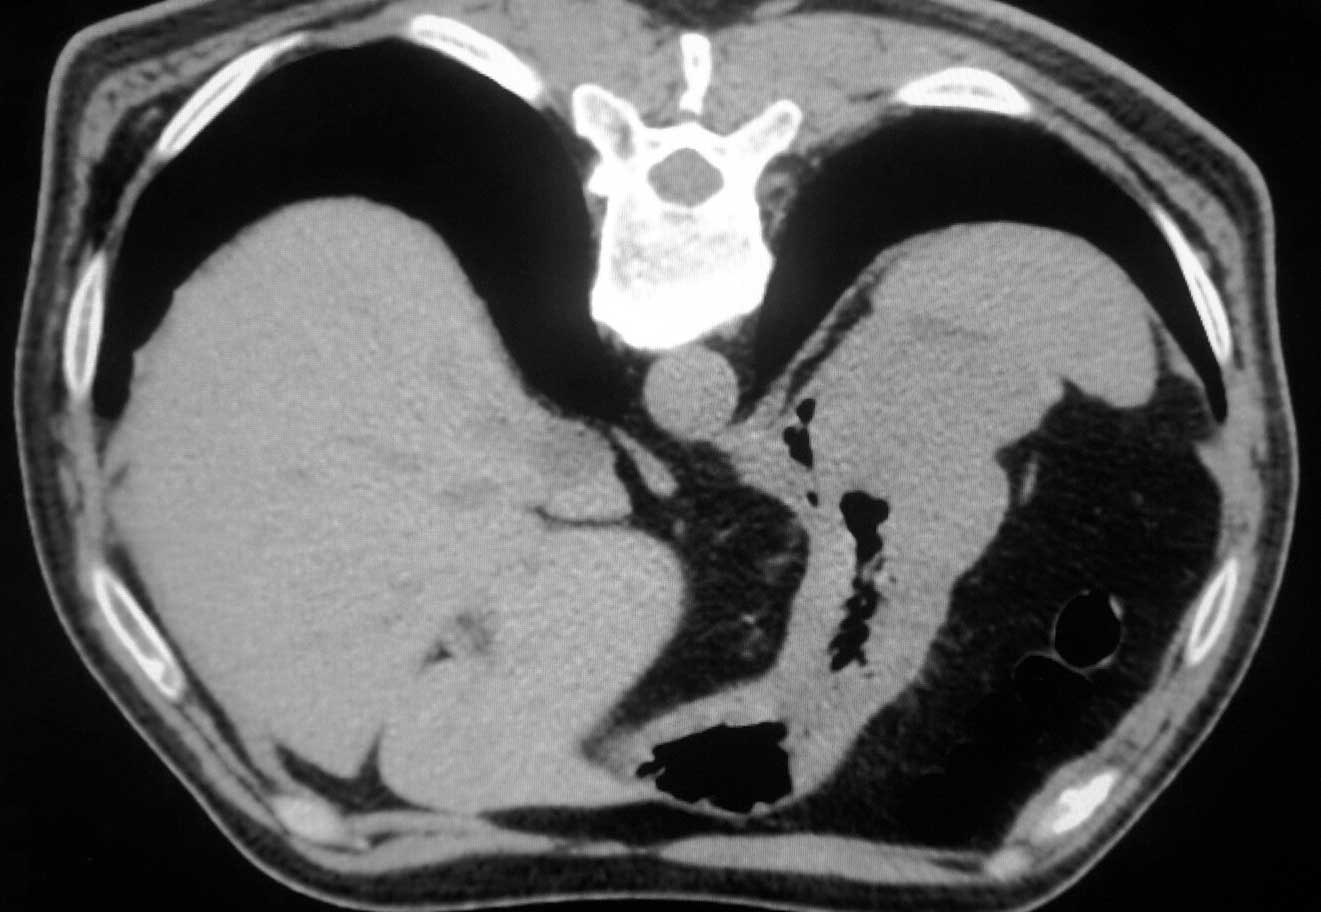

CT50125:男,60.腹痛3天入院

胃充盈不佳,胃底壁厚

病理结果胃癌

胃没充盈!图像只给看一层!大仙!!

胃癌需要进一步确诊。

胃癌可能性大,建议胃镜检查。

胃癌可能大,最好喝钡剂